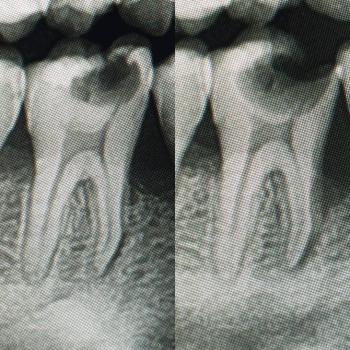

Radiographs (X-rays): They may take small periapical or bitewing X-rays to check if there is any underlying decay (radiolucency) beneath the spots, especially between the teeth.

The most significant risk that "will scale up" is active dental caries (decay).

Progression: The decay will move from the outer enamel into the softer dentin.

-

Symptoms: This causes increased sensitivity to hot, cold, or sweets.

Complication: If the decay reaches the pulp (nerve), it will result in severe pain, require a Root Canal Treatment, or potentially an Extraction. This progression can take 14 days or less if the spots are already deep. Therefore, immediate professional assessment is critical.